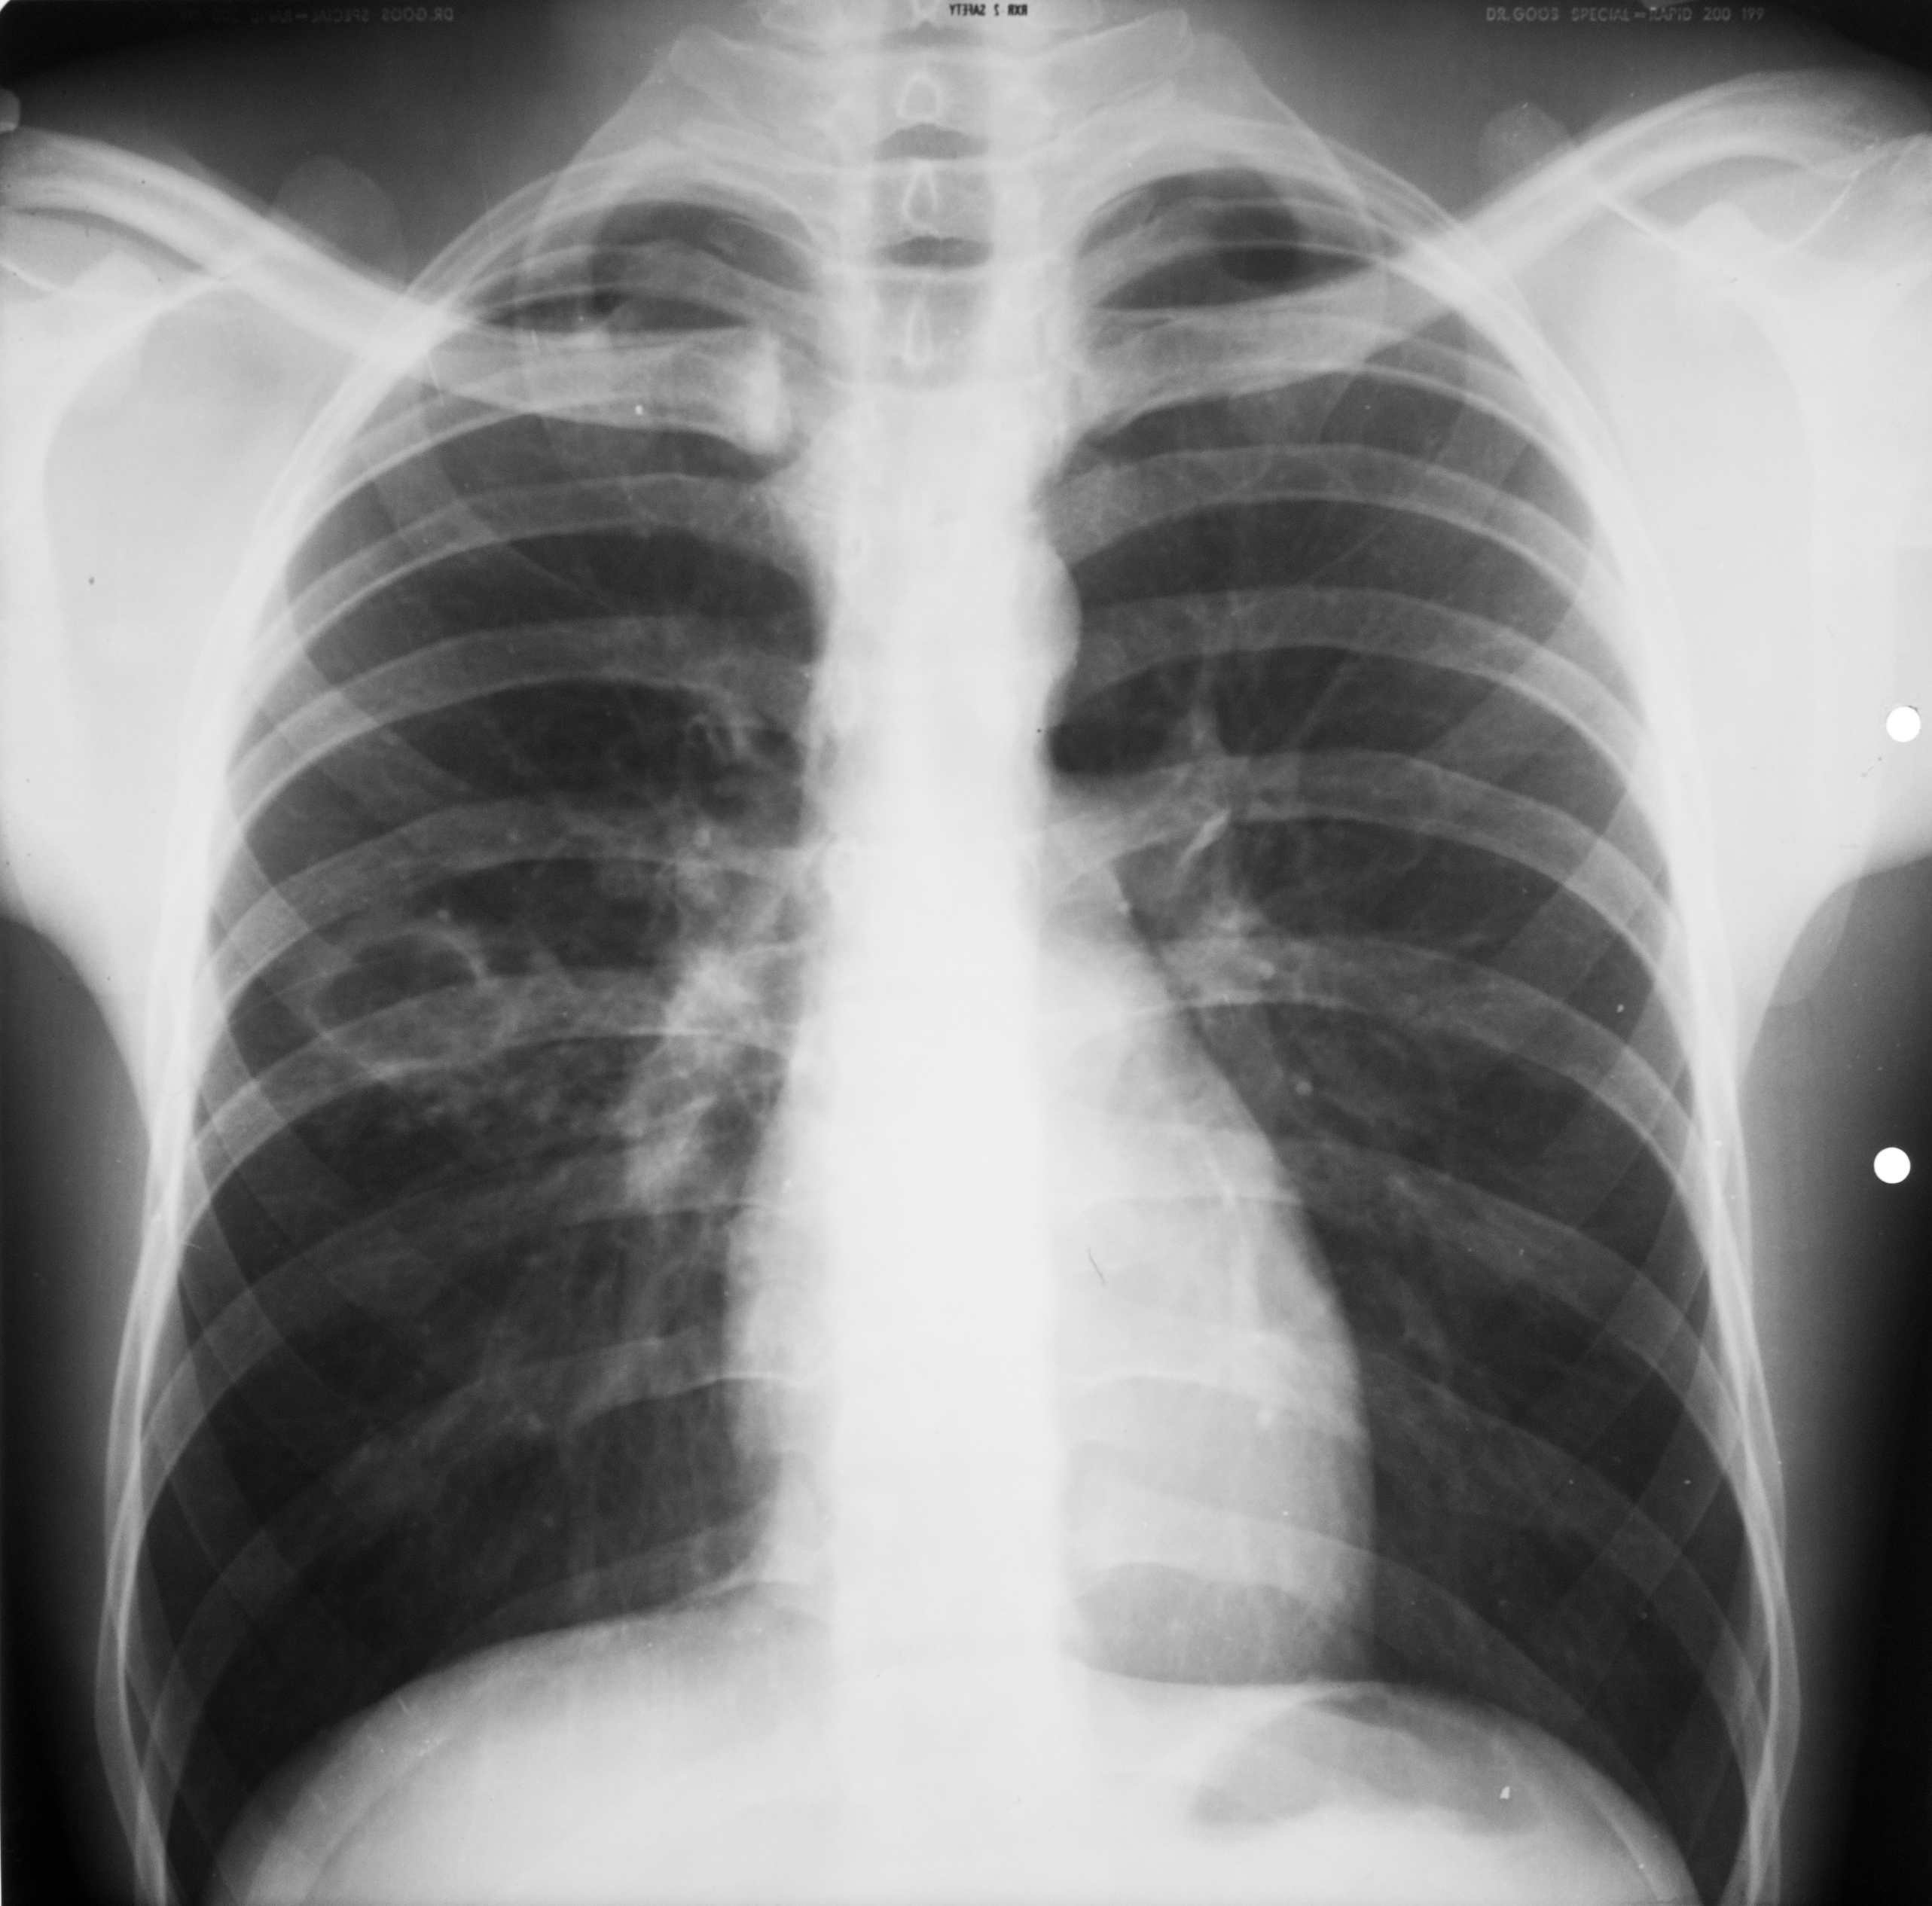

Rx toraco-mediastino-pleuro-pulmonară,incidența de față – vedem o imagine toracică normală (ITN) cu desen pulmonar,cu hil,fara nicio modificare patologică

Rx toraco-mediastino-pleuro-pulmonară – leziunea elementara : opacitate in dreapta,aprox dimensiuni,intensitate similara cu a mediastinului si o alta opacitate paracardiac de dimensiuni mai mari si intensitate mai slaba,nu știm ce sunt,presupunem noduli (sunt 41 de diagnostice diferentiale pt opacitate pulmonară

Rx toraco-mediastino-pleuro-pulmonară – opacitate la bazele plămânilor,de intensitate medie,situată la nivelul sinusurilor costo-diafragmatice,care nu mai sunt ascuțite,ci sunt închise/întinse ?,colecție pleurală

Rx toraco-mediastino-pleuro-pulmonară – opacitate pulmonară în treimea mijlocie a câmpului pulmonar drept,net liniar delimitată inferior, ........... delimitată superior,cu bronho-gramă aerică,cel mai probabil pneumonie